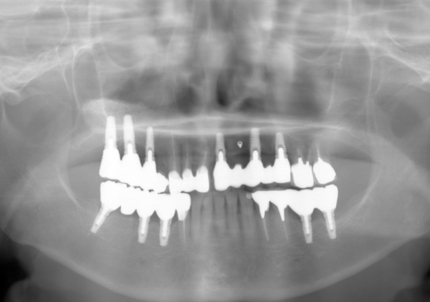

↑ 2025年9月9日

↑2008年12月

↑2024年6月26日

2023年3月レントゲン 経過良好